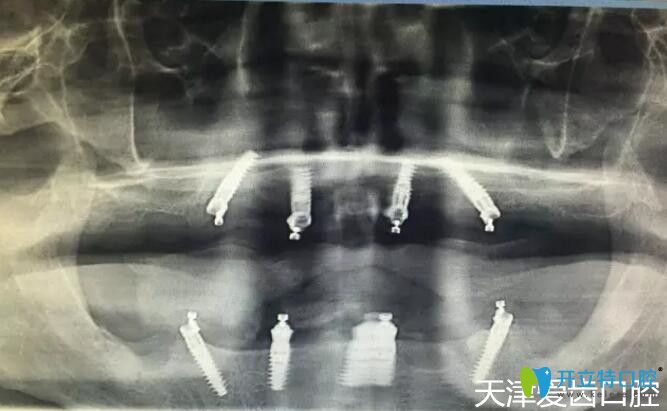

我在天津愛齒口腔做allon4全口種植牙術后CT片

郭平川醫(yī)生給我做的ALL-ON-4全口種植牙手術,從拔牙到裝上臨時牙冠,僅用了2個多小時,從手術室出來我就擁有了一口嶄新的“牙齒”,而且當天下午回家就能吃東西啦!